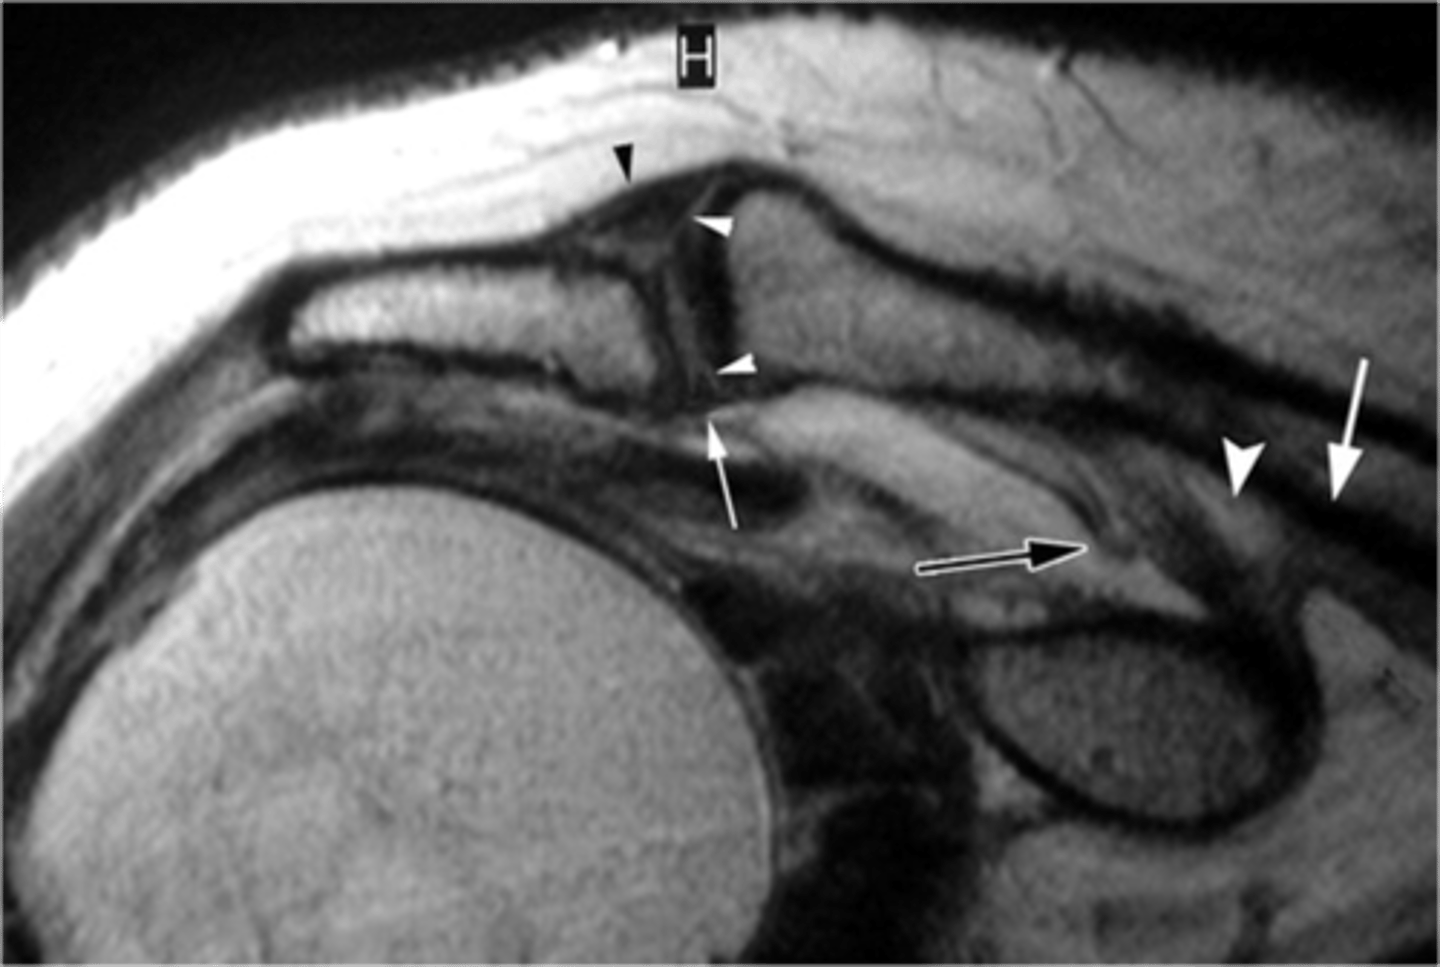

Lytic/arthritic changes in the ACJ --> hypertrophy on the inferior side --> compression on the rotator cuff --> increases the likelihood of a rotator cuff tear (i.e., the supraspinatus falls victim to bone spurs, swelling, hypertrophy, etc.)

Case: a 73-year-old swimmer fell on a boat in rough weather. There was expansion of the ACJ, impingement of the supraspinatus, erosions of articular surfaces, and subdeltoid hematoma (chronic).

Which changes may occur as a result of this accident?

Os Acromiale, a disorder that involves lack of fusion of the acromion (i.e., the growth plate did NOT fuse --> mobile acromion --> encroachment and impingement on the rotator cuff tendons)

What are these images depicting at the ACJ?